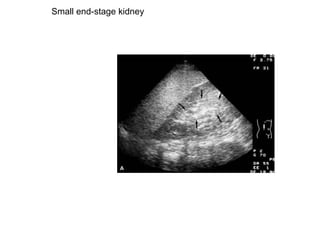

Small end-stage kidney